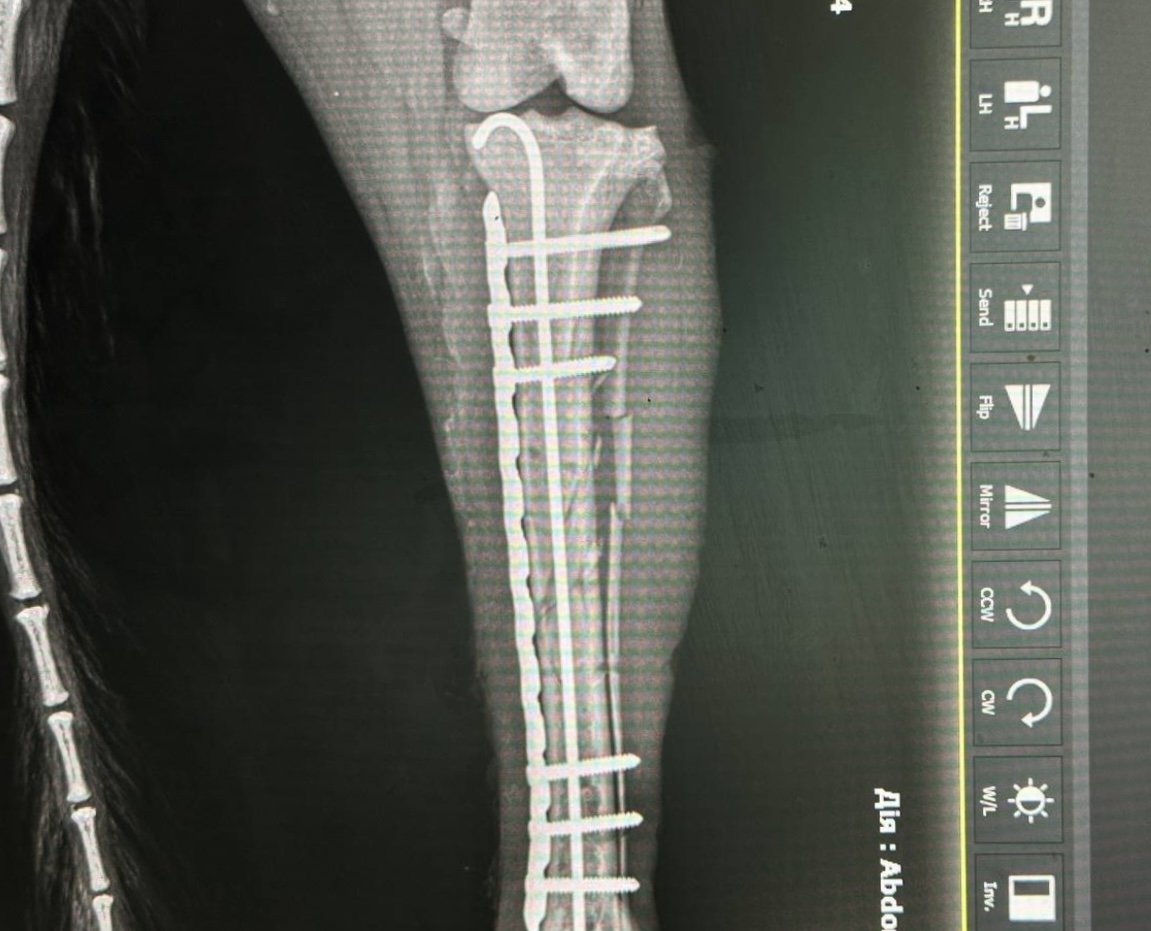

Рентгенографія – метод неінвазивного дослідження внутрішньої структури органів, які проектуються за допомогою рентгенівських променів на спеціальний цифровий перетворювач. Наш рентгенологічний комплекс є одним з найсучасніших систем на території України і видає зображення через 1.5 секунди після знімку що мінімізує час знаходження тваринки на рентген столі, час огляду і саме важливе дозу випромінення яку отримує тваринка і люди навколо, наш сучасний ветеринарний рентген настільки безпечний, що доза опромінення дозволяє без будь яких наслідків для здоров’я робити більше 300 знімків на рік.